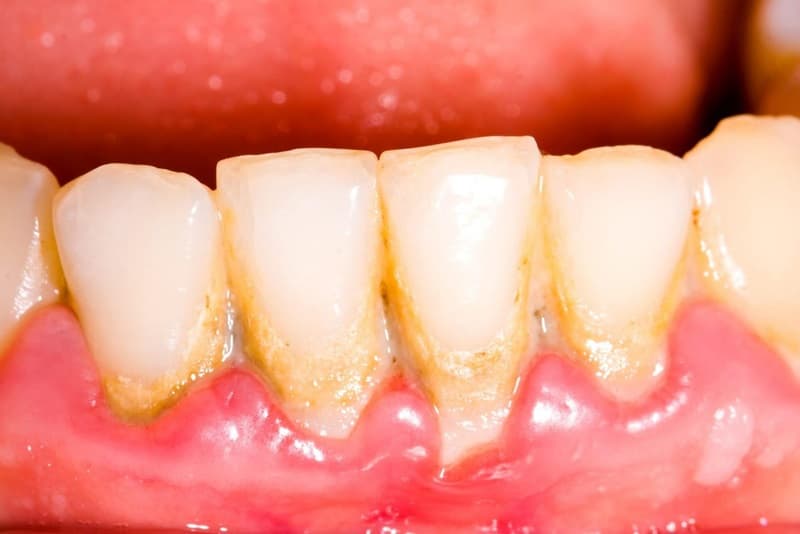

Mảng bám trên răng là một lớp màng mỏng, dính và không màu hoặc hơi vàng do vi khuẩn tạo thành trên bề mặt răng và nướu. Lớp mảng bám này hình thành khi vi khuẩn trong miệng kết hợp với các hạt thức ăn và nước bọt. Mảng bám không chỉ gây mất thẩm mỹ mà còn là nguyên nhân chính dẫn đến nhiều vấn đề về răng miệng nếu không được làm sạch kịp thời.

Mảng bám chứa vi khuẩn có thể tạo ra acid khi chúng phân hủy đường từ thức ăn và đồ uống. Acid này có thể tấn công men răng, làm suy yếu cấu trúc răng và dẫn đến sâu răng. Nếu mảng bám không được loại bỏ thường xuyên, nó sẽ cứng lại thành cao răng (tartar), tạo điều kiện thuận lợi cho vi khuẩn phát triển mạnh hơn và gây ra các bệnh lý như viêm nướu và nha chu.

Cao răng là mảng bám đã cứng lại, thường có màu vàng hoặc nâu, bám chắc vào bề mặt răng và không thể loại bỏ bằng cách đánh răng thông thường. Chỉ có thể loại bỏ cao răng bằng các dụng cụ chuyên dụng tại phòng khám nha khoa.